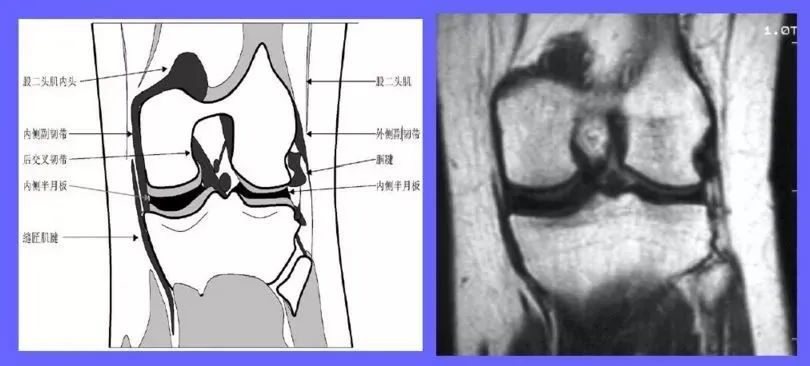

半月板损伤的磁共振表现

图片尺寸800x600